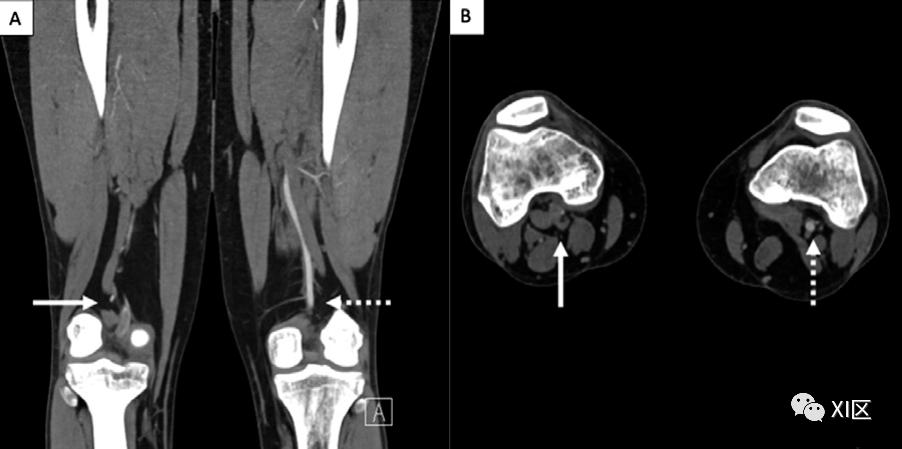

腘动脉通常在腓肠肌内侧头和外侧头之间下降到腘肌上方。腘动脉的卡压是由邻近肌肉或肌腱结构的压迫引起的(图9),卡压的来源可能是解剖性的或功能性的。解剖性卡压发生在患者的腘动脉有不典型的走向,因此与邻近肌肉的关系不正常,导致用力时压迫。功能性卡压的患者解剖结构正常,压迫是由于跖骨、内侧腓肠肌和比目鱼肌的肥大。腘动脉卡压通常表现为活动时的小腿和足部跛行。风险包括慢性血管微创伤、早期动脉硬化和血栓形成导致远端缺血。

图9 34岁男性,单侧腘动脉卡压。冠状位(A)和轴位(B)的CTA图像显示,右腓肠肌内侧头压迫右腘动脉(箭头),左侧肢体的正常解剖关系(虚线箭头)。要确定腘动脉卡压的来源,需要进行成像。CTA可以描绘出动脉的变化,并提供高的软组织对比度,可以定义腘窝内的肌肉、血管、脂肪组织和骨骼。放射学报告中应包括的动脉变化是是否存在内侧偏移、狭窄、闭塞和动脉瘤形成,以及腘窝内是否存在突出的旁路。CTA对动脉狭窄的分级和周围肌肉异常的评估很有帮助,如肌肉插入点的变化。后期处理方法包括容积渲染和多平面重建,对于检测腘动脉移位的程度和造成动脉压迫的解剖学上的变异肌肉特别有用。临床医生需要一份关于动脉变化和周围解剖结构的详细报告,以确定最合适的手术方法。